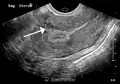

Diagnosis

Physical examination and ultrasound are sufficient for diagnosing uterine fibroids in the majority of people. When ultrasound findings are inconclusive, magnetic resonance imaging (MRI) may be able to confirm the diagnosis of uterine fibroids in most cases. In addition, MRI can identify benign uterine fibroids with atypical imaging features and fibroids with variant growth patterns. MRI can also identify other uterine (e.g. adenomyosis, endometrial polyps, endometrial cancer) and extrauterine (e.g. benign and malignant ovarian tumors, endometriosis) disorders that may mimic the appearance of uterine fibroids and/or contribute to the patient's symptoms.[38] However, a small proportion of uterine fibroids can mimic other malignant uterine tumors (e.g. leiomyosarcoma) on all available imaging modalities (e.g. ultrasound, CT, MRI and PET-CT).[38]